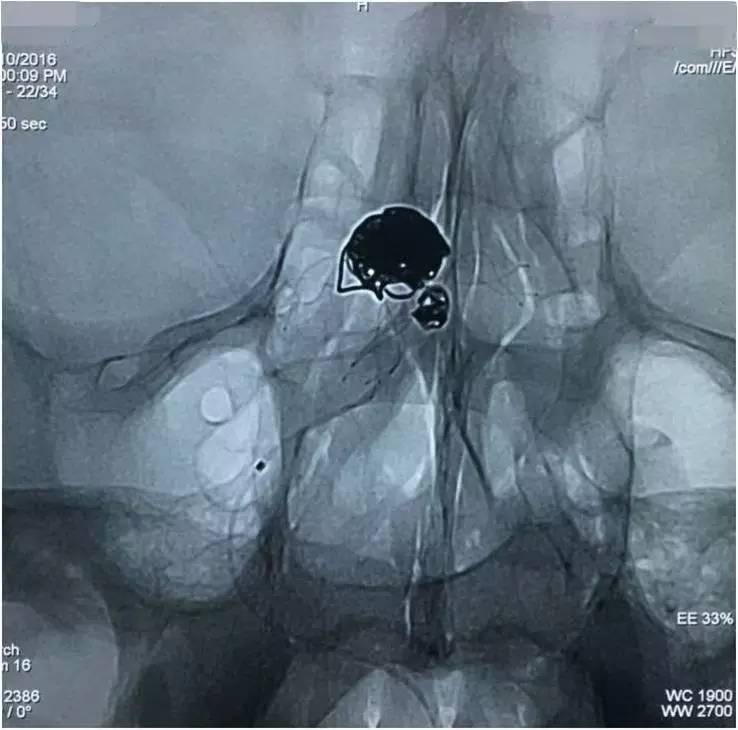

▼左椎动脉工作位造影,可以清晰暴露基底动脉顶端动脉瘤及其子瘤、左小脑上动脉瘤。

▼Headway17导入左PCA P2段,用于备放LVIS JR支架;Echelon10微导管送入基底动脉顶端动脉瘤瘤腔内,送入第一枚弹簧圈QC-4-12-3D,弹簧圈送出约一半长度,在瘤腔内盘旋,一定程度上能有助于防止后续释放的支架陷入瘤腔。

▼经预置的Headway17送入LVIS JR 3.5*23支架,跨瘤颈释放入左PCA-基底动脉内,蒙片显示支架张开良好。

▼Headway17完成支架释放后,经支架网眼导入左小脑上动脉瘤内。这里要说明的是,LVIS JR的网眼是比较容易穿过的。

▼经Headway17送入弹簧圈栓塞左侧小脑上动脉瘤。

▼Headway17完成左小脑上动脉瘤的栓塞后,再经支架网眼导入右PCA,将第二枚LVIS JR 3.5*23支架跨瘤颈释放入右PCA-基底动脉,如此完成了Y型支架的释放,为基底动脉顶端动脉瘤的栓塞工程摆好了脚手架。